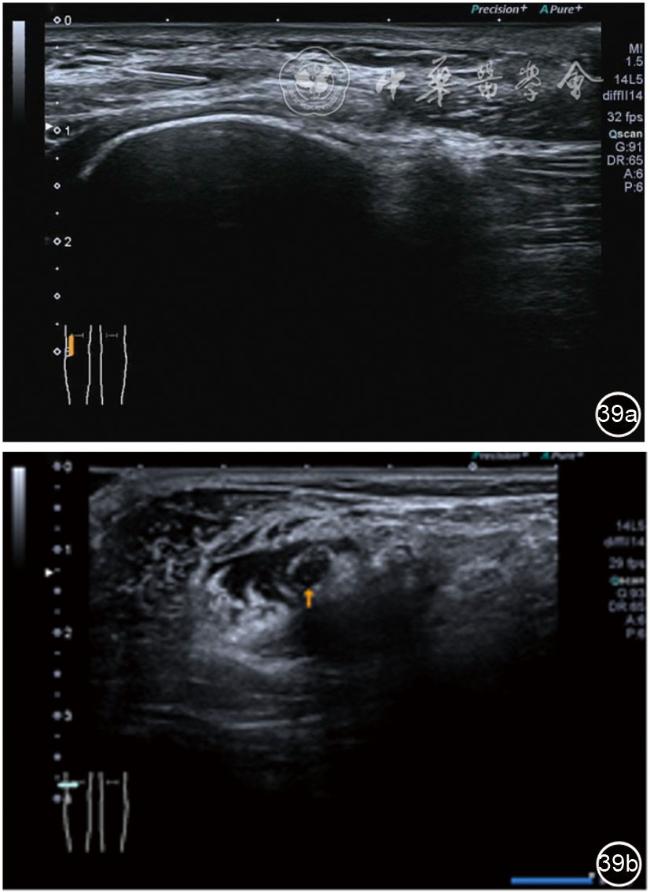

1.腓总神经卡压局部液压松解加药物注射治疗。单纯的因为体位压迫因素或者有明确的韧带压迫造成的早期腓总神经卡压,可以应用液压松解治疗,效果满意。如果治疗效果不佳,可以应用针刀对压迫韧带切割松解。患者采取健侧侧卧位,患肢在上,屈膝20°。穿刺区域常规消毒,探头涂抹耦合剂后套入无菌手套碘伏消毒或使用无菌耦合剂。将探头置于患者皮肤表面,首先扫查神经短轴切面,确定神经后旋转为长轴切面引导注射。寻找神经卡压最明显的部位(粗、细交界区),用一次性10 ml注射器,应用25G注射针头抽吸0.5%利多卡因8 ml+地塞米松5 mg,从近端穿刺(也可以从远端向近端),沿神经表面纵轴方向,确定针尖在神经膜外后推注药物进行松解(图39),长轴、短轴观察,如果液体沿着神经周围分布良好,无压迫,完成松解。拔出针头,局部压迫3分钟,创可贴覆盖。

图39 超声引导下腓总神经卡压局部液压松解加药物注射治疗